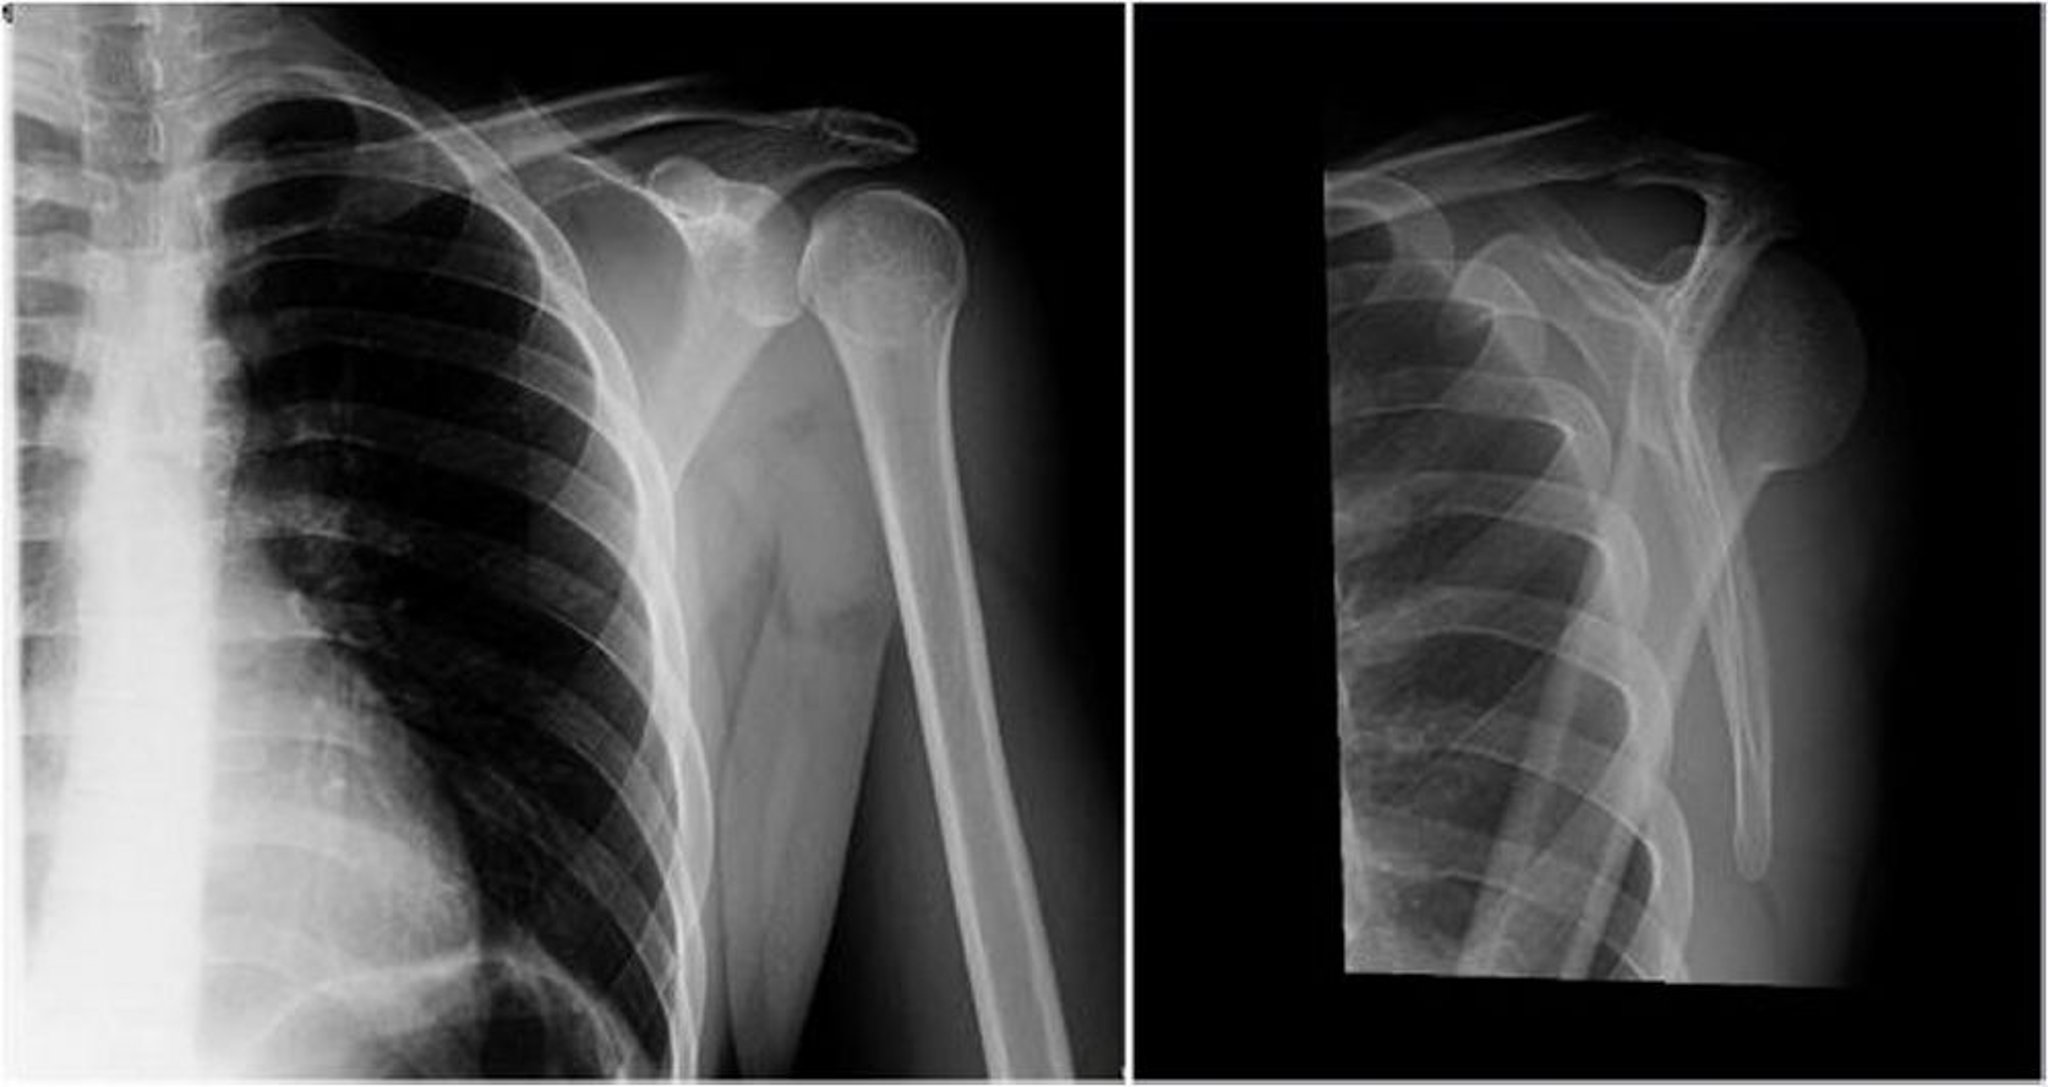

Вывих плеча назад: передне-задняя и Y-проекция

На левом снимке в передне-задней проекции головка плечевой кости повернута вовнутрь, в результате чего появляются симптомы лампочки или "мороженого-рожка" (проекции большой и малой бугристостей в боковой проекции не видны), что свидетельствует о вывихе назад. На правом изображении (вид Y) головка плечевой кости расположена позади гленоидной ямки, что указывает на задний вывих.

Image courtesy of Danielle Campagne, MD.